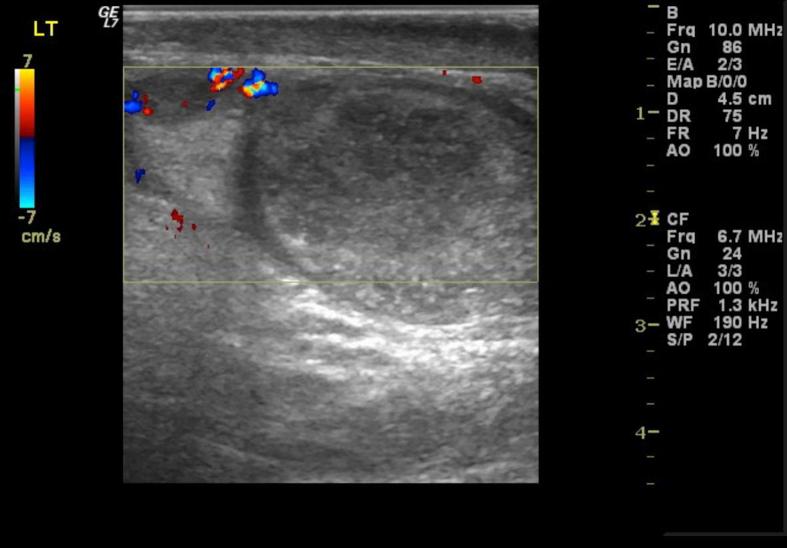

A 65 year old patient underwent EVAR for an aortic and bilateral iliac aneurysms. During the procedure, the right internal iliac artery was intentionally occluded to facilitate treatment of the common iliac aneurysm; however, the left internal iliac artery was preserved. The procedure was uneventful. On the second post-operative day the patient gradually developed symptoms of acute left testicular ischaemia. Clinical and ultrasonographic findings constituted the bases of diagnosis and the patient received conservative treatment with gradual improvement. To the authors' knowledge, this is the ninth case of testicular ischaemia after endovascular aneurysm repair reported in the literature.

一名65岁患者因腹主动脉及双侧髂动脉瘤接受了EVAR手术。术中,为便于治疗髂总动脉瘤,右侧髂内动脉被有意闭塞;然而,左侧髂内动脉得以保留。手术过程顺利。术后第二天,患者逐渐出现急性左侧睾丸缺血症状。临床及超声检查结果构成诊断依据,患者接受保守治疗后症状逐渐改善。据作者所知,这是文献报道的第9例血管内动脉瘤修复术后睾丸缺血病例。